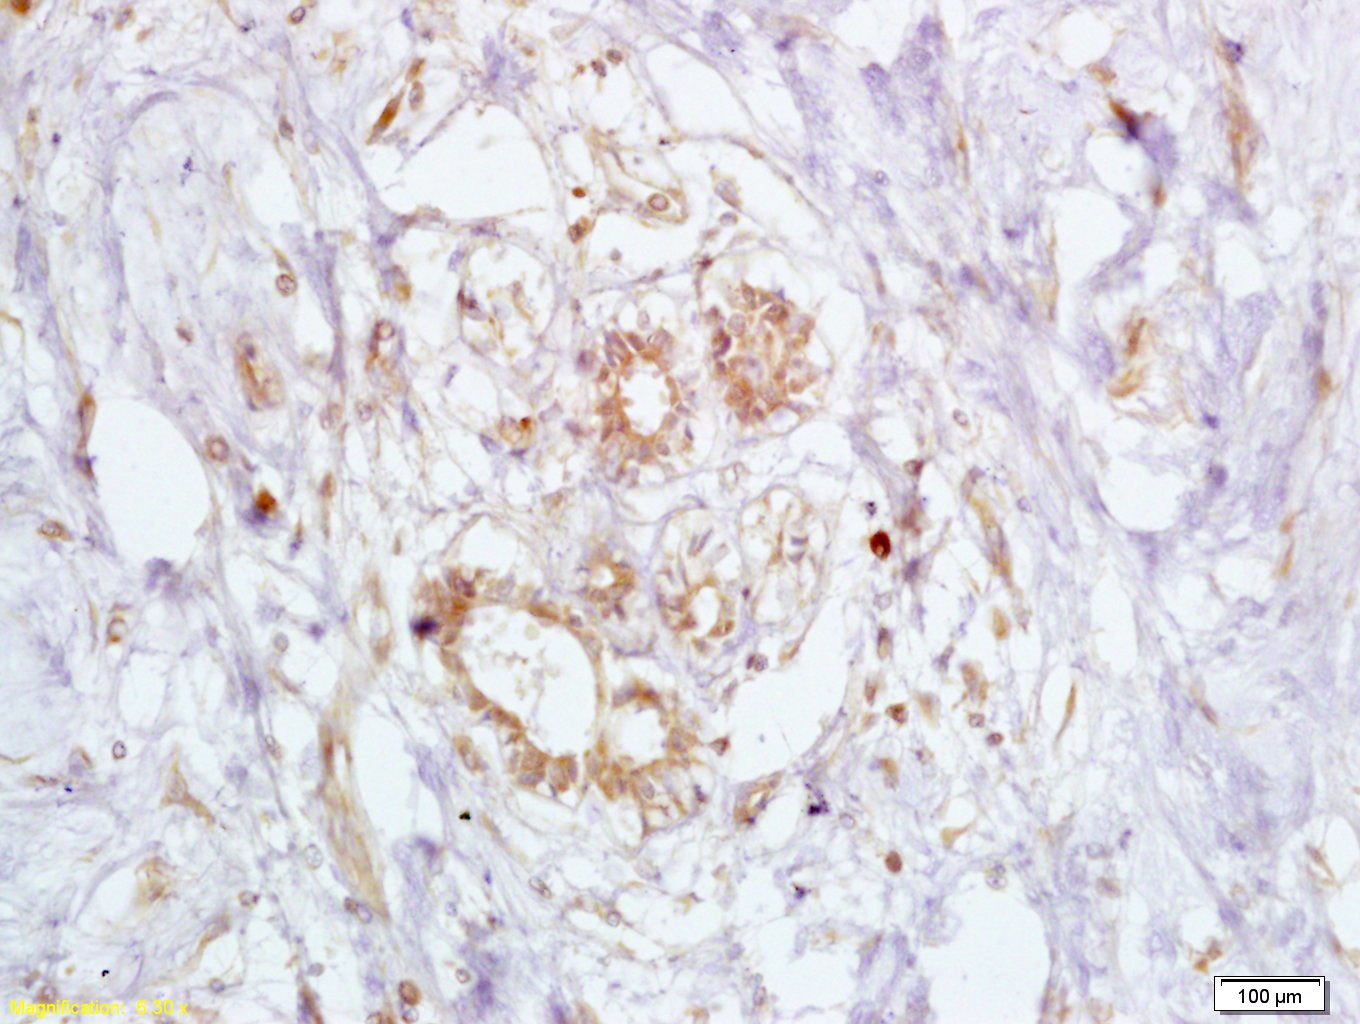

Antigen retrieval: citrate buffer ( 0.01M, pH 6.0 ), Boiling bathing for 15min; Block endogenous peroxidase by 3% Hydrogen peroxide for 30min; Blocking buffer (normal goat serum,C-0005) at 37℃ for 20 min;

Incubation: Anti-BRCA2/FANCB Polyclonal Antibody, Unconjugated(bs-1210R) 1:200, overnight at 4°C, followed by conjugation to the secondary antibody(SP-0023) and DAB(C-0010) staining